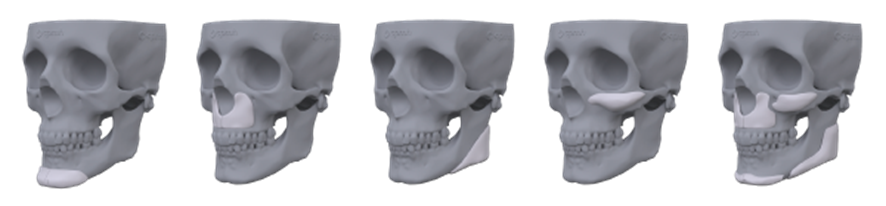

Tipos de próteses faciais

As opções trazidas pelo planejamento 3D, com as possibilidades do paralelismo facial, se associam ao uso do PMMA como ferramentas poderosas para potencializar os resultados nos pacientes.

São próteses personalizadas fabricadas especificamente para cada caso

Planejamento virtual milimétrico e detalhado para visualizar o resultado da cirurgia

Fabricação personalizada das próteses